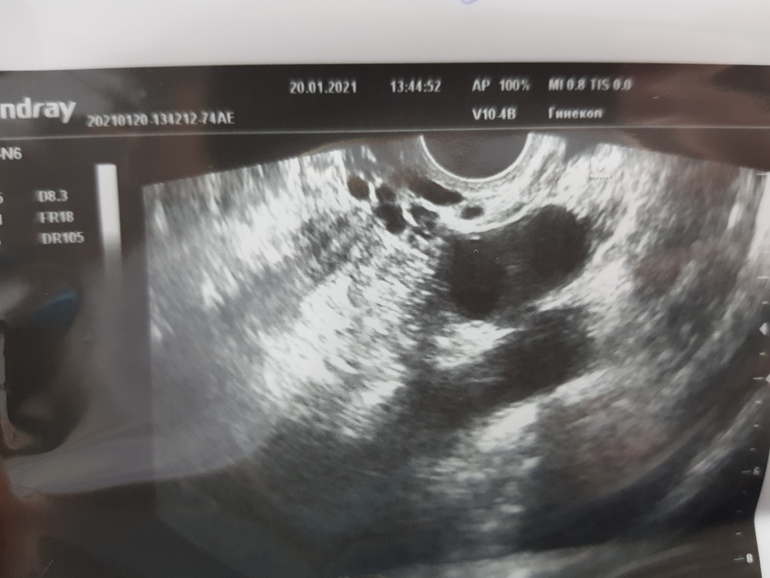

День цикла 11й.

Была на узи на 8й: ЛЯ 16мм, ПЯ 16, 14, 14

На 11й: ЛЯ 19мм, ПЯ 16, 15, 14.

Сказала все фоликулы. На 8й врач думала кисты, но я на стимуляции и проверяла до, что кист нет.

Где-то на этих фотах спряталось аж 4 штуки, сказали дф, но должны быть уже жт. На стимуляции.

По мне так больше похоже на дф - достаточно четкие контуры, а врач что?

На 8й дц было 16мм один дф в левом и 16, 14, 14 в правом. На стимуляции.

А на 11й дц сказали что 19мм один в левом и 16, 14, 14 в правом.

Вот я и думаю как так, до 8го дц вымахали и замерли.

Больше на дф похоже, контуры уж больно четкие, жт немного иначе выглядит

Я ожидала что будут жт (до 4х, на стимуляции), но мне сказали что ДФ. Просто на 8й дц они были 16, 16, 14, 14, а на 11й стали 19, 16, 14, 14.